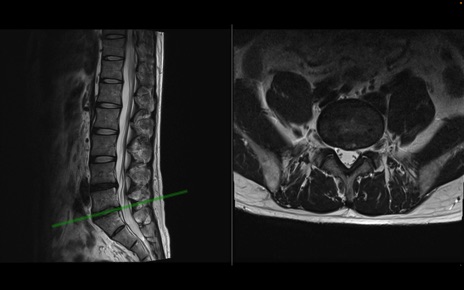

【整形】TIPS症例1 腰椎MRI 横断像と矢状断像

【症例】40歳代男性

【主訴】左臀部〜大腿後面痛み

【現病歴】2週間前から腰痛あり。2日前に夜中にくしゃみをした際に激痛が出現。疼痛強いため来院。

【身体所見】左臀部〜大腿後面、下腿後面のしびれ。SLR -/+ 30度、うつ伏せ困難、筋力低下なし。

異常所見と診断は?